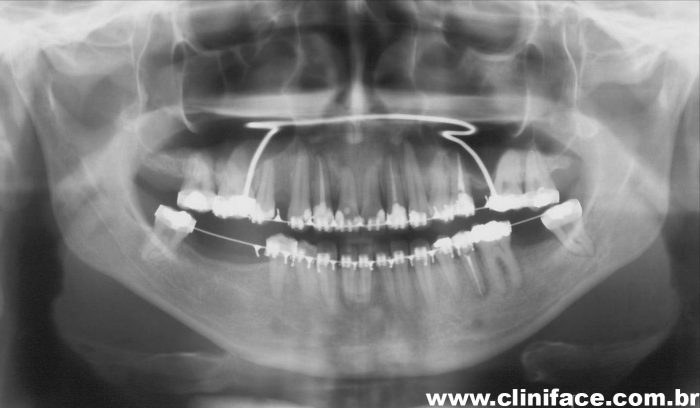

Raio x panorâmico inicial  - Clínica Cliniface

Raio x panorâmico inicial